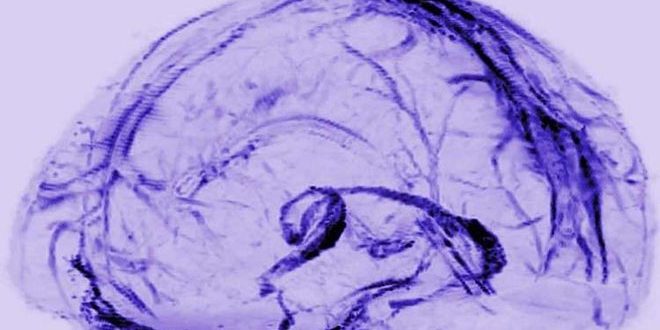

اكتشف العلماء أخيرا سر كيفية تخلص الدماغ من المخلفات أو المواد السامة، حيث أنه يملك أنابيب صرف خاصة به قادرة على القيام بهذه المهمة ولأول مرة، وجدوا الأوعية التي تنقل المواد الضارة أو الخلايا الميتة خارج الدماغ للحفاظ على صحته.

وكان الدكتور رايش وفريقه استخدموا تقنية التصوير بالرنين المغناطيسي لمسح أدمغة خمسة متطوعين أصحاء بعد حقنهم بصبغة مغناطيسية مصممة لإظهار الأوعية، وهو ما مكنهم من الوصول إلى هذه النتائج المفاجئة بوجود نظام لمفاوي في الدماغ، ويمكن لهذه النتائج أن “تغير بشكل جوهري طريقة تفكيرنا في كيفية ربط الدماغ بالجهاز المناعي”.

ويبدو أن الأوعية التي اكتشفها الفريق مماثلة لتلك الموجودة في الجهاز اللمفاوي الذي يعمل بمثابة شبكة صرف صحي خاصة بالجسم والتي تعمل جنبا إلى جنب مع الأوعية اللمفاوية، لإزالة النفايات ومراقبة الجسم لرصد ما إذا كان الجسم يتعرض للهجوم من البكتيريا أو الفيروسات أو التعرض لإصابة وحتى وقت قريب لم يكن هناك أي دليل على أن النظام اللمفاوي يمتد إلى الدماغ مما جعل العلماء يعتقدون بأن الدماغ يعتمد وسيلة مختلفة للتخلص من المخلفات.